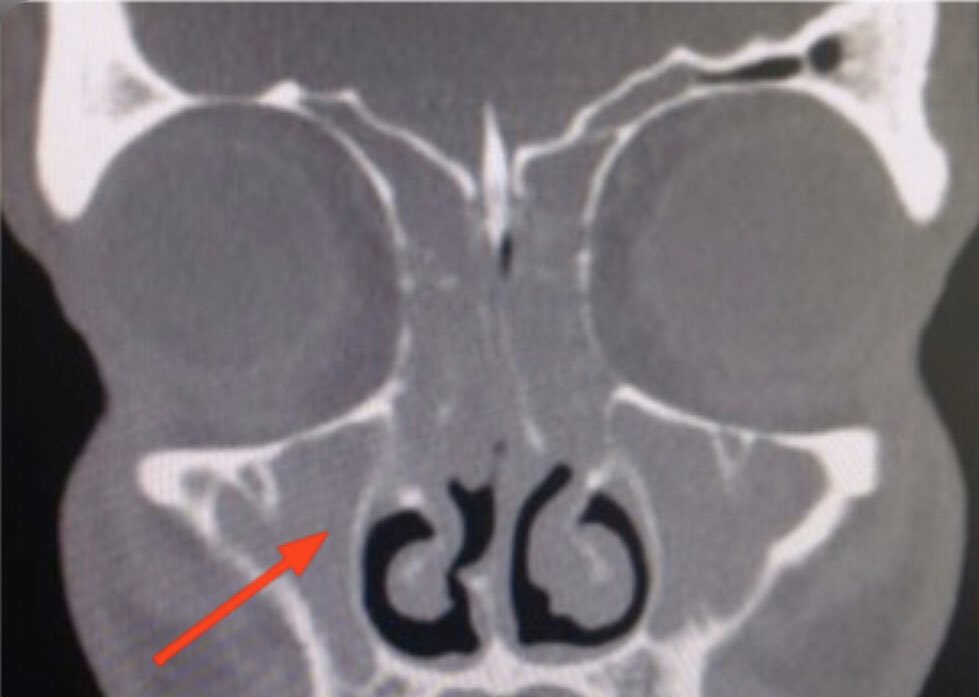

- متلازمة الكحة لمجرى التنفس العلوي او ما يعرف ب upper airway cough syndrome.

ويستوجب عمل تصوير للجيوب الأنفية.